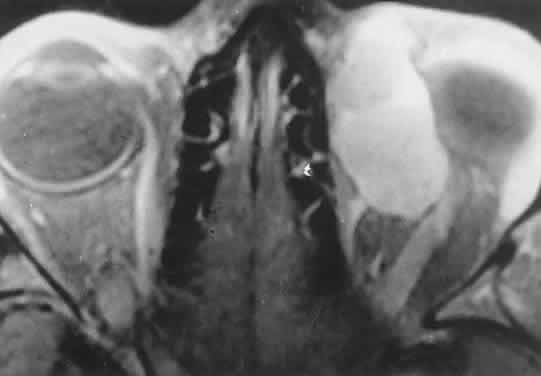

Acute blood cyst formation in this age group makes the distinction between a pre-existent but clinically silent lymphangioma and a rapidly emerging rhabdomyosarcoma a common orbital diagnostic problem. Evidence suggesting an orbitallymphangioma includes the variable finding of conjunctival or eyelid components of the malformation.86 Conjunctival lesions appear as ectatic channels filled with clear or hemorrhagic fluid. Eyelid ecchymosis may result from the seepage of blood out of the thin-walled orbital cysts. Additional developmental anomalies of the eye and adnexa may be present. Other head and neck involvement may be manifest as local hypertrophy (e.g., of the cheek or lips), and cystic palatal lesions may be seen. CT discloses a single or multilobulated mass, which represents only the blood cyst portion of the tumor (Fig. 14). Individual lobules may have different radiodensities depending on the presence of clots or liquefied blood within each cyst (Fig. 15). A generalized increase in orbital dimensions suggests a long-standing, probably congenital process. Echography may help differentiate the cystic components of lymphangioma from cellular rhabdomyosarcoma. Echography shows the blood cysts to be acoustically inactive spaces, with extremely low internal reflectivity (Fig. 16). Clots within the cysts can increase internal heterogeneity, however. MRI has virtually eliminated the need for diagnostic biopsy in this condition, because of its ability to show differing magnetic properties of suspended, degrading blood products (Fig. 17).

The intimate association of orbital lymphangiomas with structures critical to normal vision makes their complete excision almost impossible without incurring vision loss. Because their vascular components do not actively proliferate, the response to radiation therapy is limited and probably is proportionate to whatever lymphoid tissue is present. The presence of a blood cyst is not in itself an indication for treatment if vision is not impaired. In many cases, the blood resorbs during several weeks without residual problems. Frequently, however, vision is compromised by the sudden expansion of multilobulated cysts that surround the optic nerve, and simple observation may result in permanent deficits. Treatment requires evacuation of the offending cysts in a conservative manner consistent with preservation of vision.84 Because the channels of a lymphangioma are hemodynamically isolated from the systemic circulation (“no flow anomalies”),63 their surgical decompression does not produce brisk new bleeding from within them. Rather, the hemorrhagic risk of surgery involves intraoperative and, more often, postoperative, intrinsic bleeding, creating new blood-filled macrocysts.62 Conservative surgery restricts intraorbital manipulation, involves evacuation of offending blood cysts, and avoids disturbance of nonexpanded portions of the lymphangioma. Extensive dissection for cosmetic purposes should be undertaken with the same respect for the fragility of nonexpanded channels. TRAUMATIC ORBITAL HEMATOMA Although the diagnosis of a traumatic orbital hematoma would seem obvious on the basis of history alone, some element of trauma within a few days of the onset of proptosis is such a common historical finding among small children that it may have little differential value. Conversely, a history of culpable trauma may not always be forthcoming, as in cases of child abuse. In penetrating orbital injuries, the entry wounds suggest the diagnosis. Retained foreign bodies should be ruled out. In blunt injuries, other diagnostic clues are helpful. Ecchymosis may be present but also may be a feature of granulocytic sarcoma, neuroblastoma, or lymphangioma with recent bleeding. CT may show an associated fracture. Most orbital hematomas that result from blunt injury occur in the potential subperiosteal space (Fig. 18). The lack of adjacent sinus opacification and the absence of systemic toxicity differentiate this entity from a subperiosteal abscess, which can have a similar appearance.59 Echography shows the low acoustic reflectivity characteristic of fluid-filled spaces. If a traumatic orbital hematoma has compromised vision by acutely elevating orbital pressure, the pressure should be reduced promptly with a lateral canthotomy and cantholysis. If, conversely, vision is compromised because of extreme globe displacement and optic nerve attenuation, the hematoma should be evacuated.87 This is a relatively simple procedure if the blood is compartmentalized in the subperiosteal space. We favor a lid crease incision, with dissection between orbicularis muscle and orbital septum to the orbital rim. The subperiosteal space is then entered, and the hematoma is evacuated. If vision is not compromised, patients can be treated conservatively. Spontaneous absorption generally follows, but hematomas occasionally enlarge with osmotic imbibition. DERMOID CYST Dermoid and epidermoid cysts often occur in the orbit and paraorbital region. Epidermoid cysts are lined by stratified squamous epithelium and are filled with desquamated keratin. The walls of dermoid cysts include dermal appendages that contribute sebum, sweat, and hair shafts to the cyst contents. Both forms probably result from abnormal invagination of surface ectoderm during fetal development. Differences may relate to the depth of tissue that has been sequestered or to the degree of ectodermal differentiation at the time of inclusion.88 Most dermoid cysts are closely related to bone suture lines, suggesting that the surface ectoderm has been trapped between fusing mesodermal processes. Dermoid cysts are most often encountered at the frontozygomatic articulation but can occur at other suture lines, including those deep in the orbit. Most lesions are anterior and paraorbital (Fig. 19), located between the orbicularis muscle and the periosteum overlying the orbital rim, and have a fibrous stalk to the suture line. Anterior cysts produce minimal bone change. Other lesions may be entirely intraorbital, causing proptosis and globe displacement. Their expansion produces an overall increase in orbital volume as well as local bone changes (Fig. 20). Dermoid and epidermoid cysts also may be largely intradiploic, with expansion into the anterior cranial fossa, the temporal fossa, or the orbit. Dumbbell lesions may be present with narrow intraosseous components. Anterior, paraorbital dermoid cysts usually are evident soon after birth. Deeper lesions may not declare themselves until mid- or late childhood, or even the adult years. Expansion of the cysts generally is slow and linear, reflecting continuous desquamation of keratinizing epithelium. There may be a point at which the pressure within the cyst inhibits further proliferation and sloughing of epithelial cells, accounting for the clinically observed stability of many lesions. Sporadic enlargement may be caused by hormonally influenced sebaceous gland secretion or by rupture of the cyst wall with a granulomatous inflammatory response to the cyst contents (see Figs. 19B-D). Such episodic change in an otherwise gradual growth pattern places intraorbital dermoid cysts into the current differential diagnosis. Anterior lesions generally are diagnosed and removed without difficulty, although their occasional occurrence near the lacrimal excretory system can complicate treatment.89 Surgeons should strive for excision of an intact cyst, because residual epithelial elements can lead to recurrence. CT examination of deeper lesions discloses a cystic mass with some internal heterogeneity caused by the different radiodensities of keratin clumps and oily secretions (see Fig. 20B). Bone changes, from shallow fossas to spherical defects, are smooth, with a sclerotic margin and a punched-out appearance. Based on the CT findings, the differential diagnosis includes cholesterol granuloma and unifocal eosinophilic granuloma. Superomedial orbital dermoid cysts must be distinguished from meningoencephaloceles before surgical intervention. Most intraorbital cysts can be removed through a lateral or anterior orbitotomy. The walls of deep lesions may be intimately attached to adjacent bone and may not peel off intact. Gentle use of a high-speed steel burr can facilitate complete removal of the cyst lining. ANEURYSMAL BONE CYST Aneurysmal bone cyst is an uncommon, benign tumor-like lesion of unknown origin.90 Most lesions present in the second decade with pain and swelling. Any bone may be involved, but the long bones and vertebrae are most often affected. Aneurysmal bone cyst of the orbital roof is an unusual cause of rapidly progressive proptosis.91 In one case, a 16-month-old boy was affected.92 The lesions both erode and expand cancellous and cortical bone.90 They are surrounded by a shell of periosteal new bone that prevents their extension into soft tissue. MRI may show fluid-fluid levels indicative of hemorrhage.92 In some cases, aneurysmal bone cyst appears to be a pathophysiologic change superimposed on a pre-existing lesion, such as a giant-cell tumor.90 In most cases, however, the bone cyst is considered a distinct pathologic and radiologic entity. Treatment of facial lesions with intralesional resection or curettage has a substantial rate of recurrence. Recurrence can be reduced with marginal resection or cryotherapy. INFLAMMATORY PSEUDOTUMOR Idiopathic inflammatory pseudotumor (IIPT) is a general term applied to those orbital inflammations without an identified inciting agent and with a sparsely cellular, mixed inflammatory infiltrate that does not suggest a systemic disease. Despite efforts to replace the pseudotumor designation, the term remains entrenched in the literature.93 However, the spectrum of clinical and pathologic conditions included under the rubric has been narrowed and refined since the term was first applied a century ago. IIPT can occur in the first 2 decades of life as well as in adulthood, and it may affect children as young as 3 years of age.94 There appears to be no sex predilection. The condition can be subdivided topographically into myositis, dacryoadenitis, episcleritis/tenonitis/perineuritis, and a localized mass. However, combined forms are common, and even when the process is centered in one structure, inflammatory changes appear microscopically and in imaging studies to spill into adjacent tissues. Among these variants, orbital myositis and dacryoadenitis are the most common forms of IIPT encountered in children. Local tumefactions may occur anywhere in the orbit. When they involve the crowded orbital apex or superior orbital fissure, they can produce the Tolosa-Hunt syndrome of painful ophthalmoplegia. The typical patient with IIPT has an abrupt onset of pain, proptosis, eyelid edema, chemosis, and conjunctival vascular engorgement.94 The left orbit is affected twice as often as the right, but bilateral orbital involvement, either simultaneous or separated by variable intervals, occurs in almost half of the pediatric cases. Among children with IIPT, there is a higher incidence of iritis than among adults with this disorder. Optic nerve head edema is noted in one-third of cases. Systemic complaints are variable but may include fever, malaise, anorexia, and nausea. Orbital symptoms may follow an upper respiratory tract infection. In pediatric cases, laboratory abnormalities may include peripheral blood eosinophilia and elevations of the erythrocyte sedimentation rate, complement level, and antinuclear antibody titer.95 The absence of a marked leukocytosis with a left shift should help differentiate this condition from bacterial orbital cellulitis. Orbital myositis may represent a greater proportion of cases of IIPT in childhood than in adulthood, and involvement of multiple extraocular muscles may occur more frequently in children than inadults. In orbital myositis, early diplopia and increased discomfort with attempted eye movement are typical symptoms. CT may show enlargement of one or more extraocular muscles in one or both orbits (Figs. 21 and 22). When a single muscle is involved, the specter of a primary or metastatic neoplasm within the muscle may be raised. However, external inflammatory signs, considerable pain and limited motility, and an explosive onset of symptoms within 24 hours all suggest orbital myositis. The uniform enlargement of the muscle, including its tendinous insertion (see Fig. 22), also helps distinguish the process from a neoplasm, which might be expected to produce a more focal, globular expansion. Echography may support the diagnosis of inflammation by showing edema in the episcleral space as a relative sonolucency between the scleral and orbital fat echoes (Fig. 23). Its CT counterpart is an increase in the radiodensity and thickness of the ocular tunica.